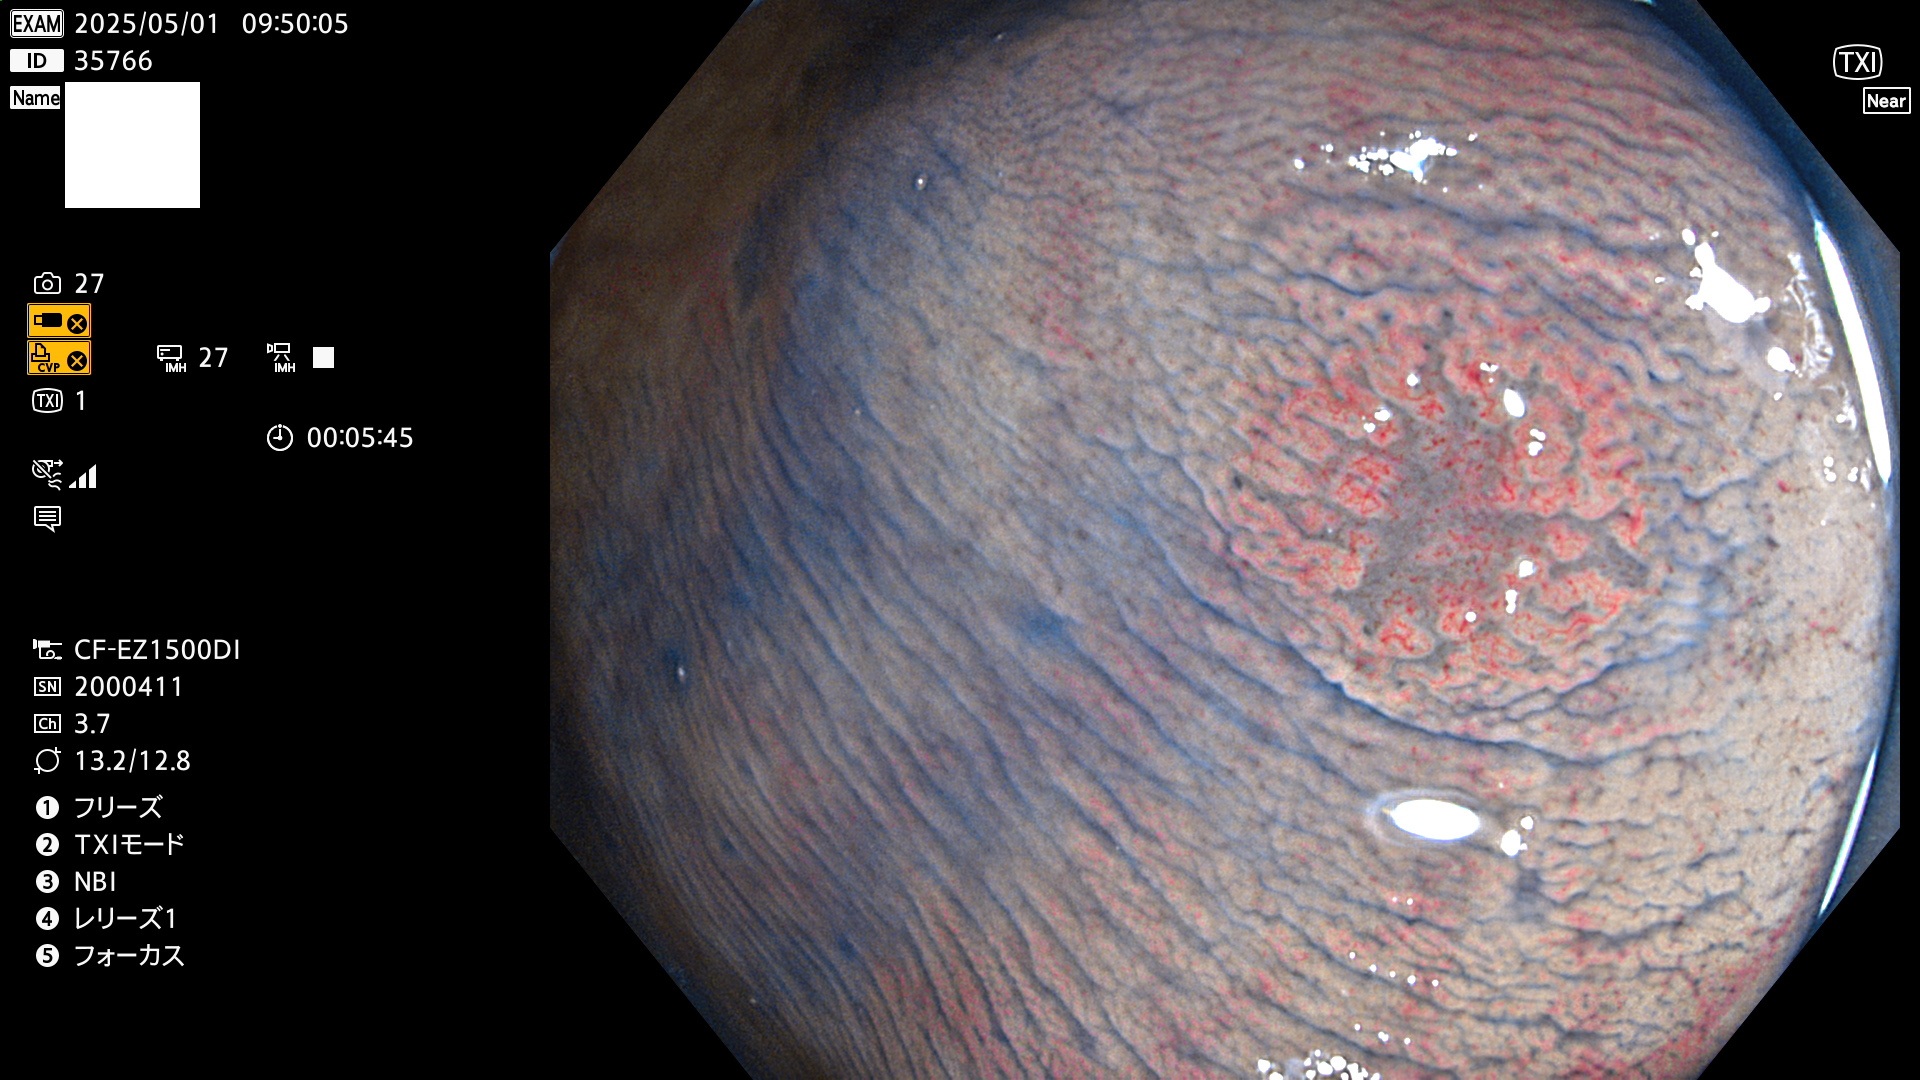

完全に平坦な物をUb、陥凹している物をUcと呼びます。Ubは認識が困難で、Ucはびらん(炎症)と紛らわしいために見落とされやすく、「内視鏡後・大腸癌」の原因になります。

抽出の対象期間 2025年5月1日〜5月2日の2日間(23件の検査)4個 (4/23=17%)